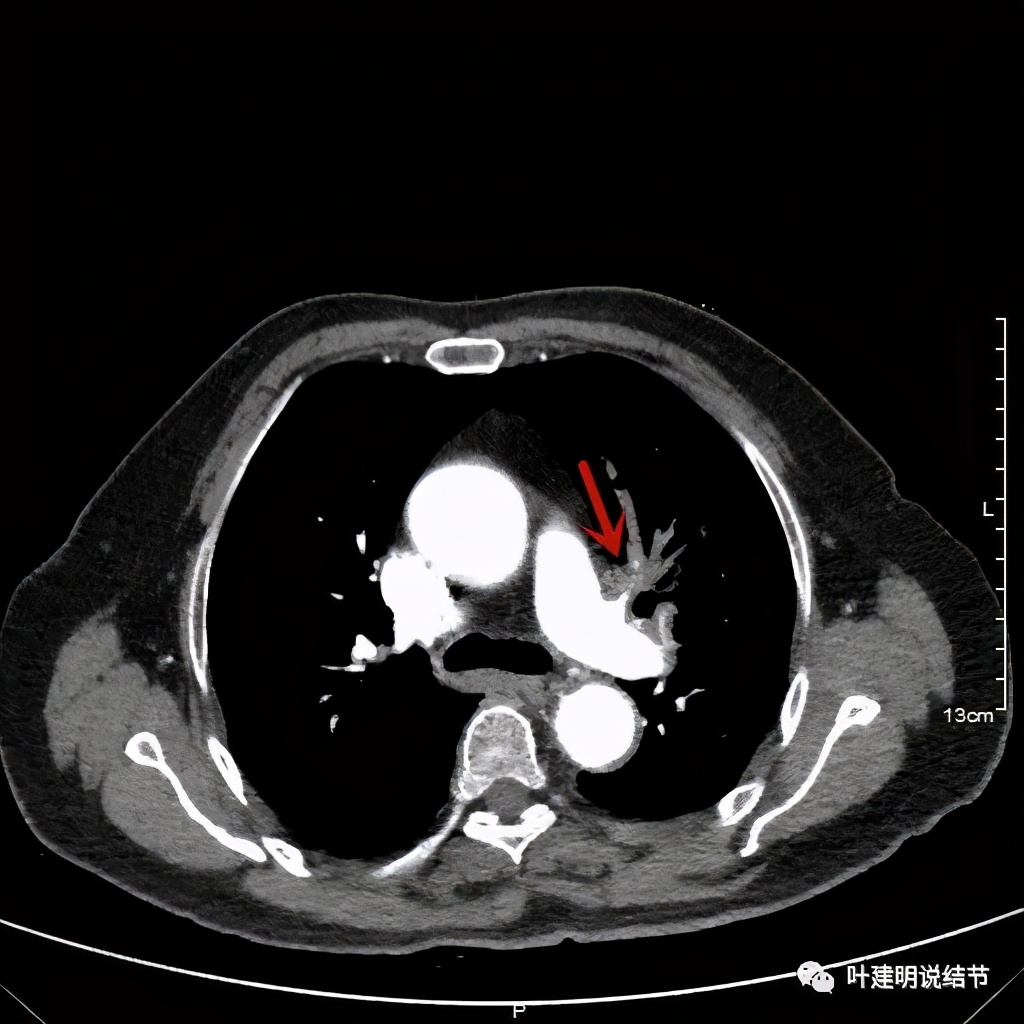

左上肺基本已经不见肿瘤,只在主动脉旁少许软组织影

上图示主动脉弓水平仍见软组织影